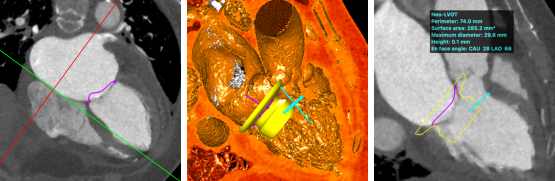

术前,陈茂教授带领团队基于详尽的CT评估测量,判断评估患者术中风险并选择适合的手术策略。通过CT影像分割三维二尖瓣瓣环、测量其径线、计算二维投影径线并模拟植入HighLife TSMVR瓣膜,判断人工瓣膜与毗邻组织贴靠位置良好且无左室流出道梗阻风险。但该例患者二尖瓣装置结构较为特殊,存在风湿性病变所致腱索增粗、短缩、融合,为导丝成环步骤带来挑战,术中输送器需要始终保持合适深度,且导丝成环过程中需始终保持高位(靠近二尖瓣环底部位置)环绕腱索形成通路,以避免植入固定环时位置靠下导致瓣膜释放时移位。